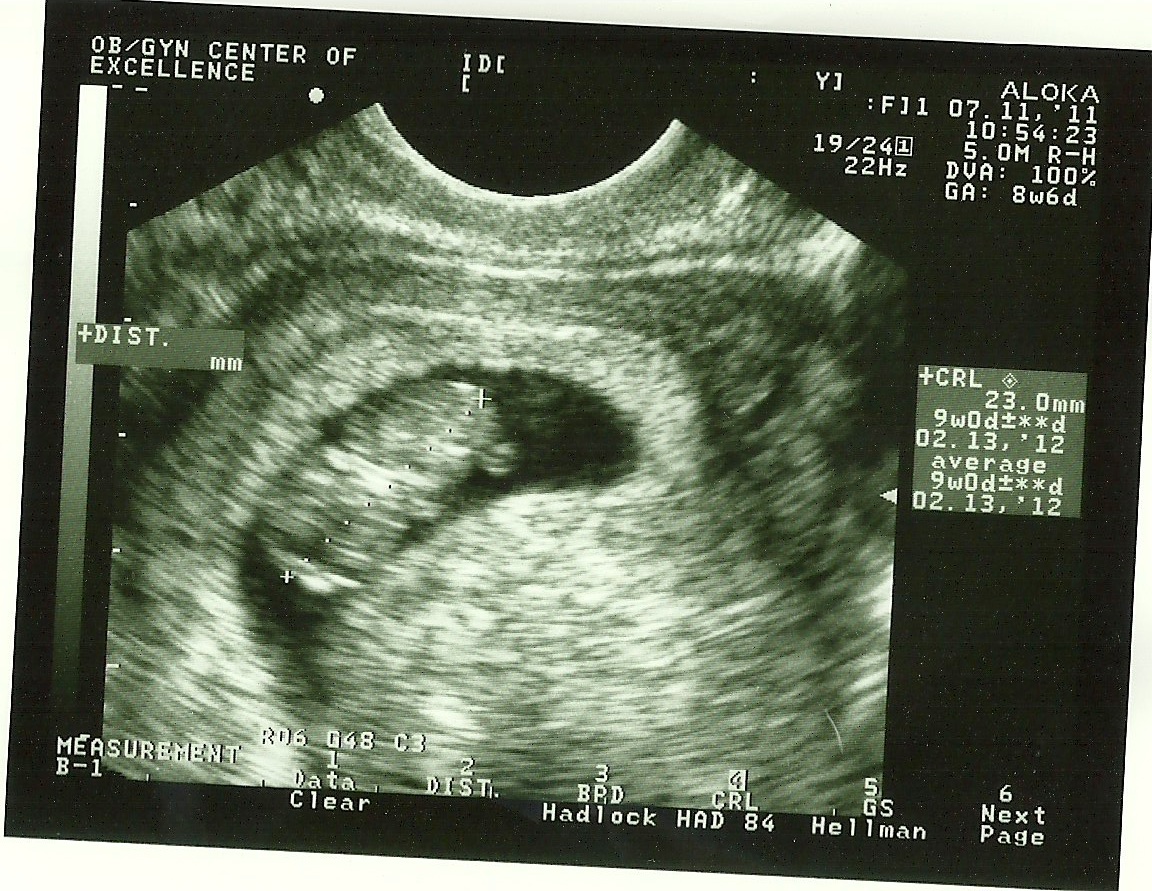

Ok, the last two look like an alien (like, a real alien), but the first one is a BABY!!! You can see it's sweet little face with his/her hand right there. This was my first abdominal ultrasound (and my 4th overall), and I was concerned they wouldn't be able to see the baby since I'm not showing yet... wrong! There it was! It (so weird to call it an "it"... I totally think it's a girl) was facing out, so we saw it like in the last 2 pictures for a while, then all of a sudden she started doing gymnastics (my kid, for sure!)! All you mamas can go ahead and laugh at me, but I was freaking. out. Laughing, crying, shrieking. Dr. B was laughing with me because I was enjoying it so much! I kept saying to David "Did you see that?!? Did you see THAT??" It is such a miracle that a tiny little 2.5" creature is already such a complete human inside of me, but you can't see it or really tell it is here yet.

So many thoughts flood through my mind as I look at these images... more than anything, thank you, Jesus for this baby.